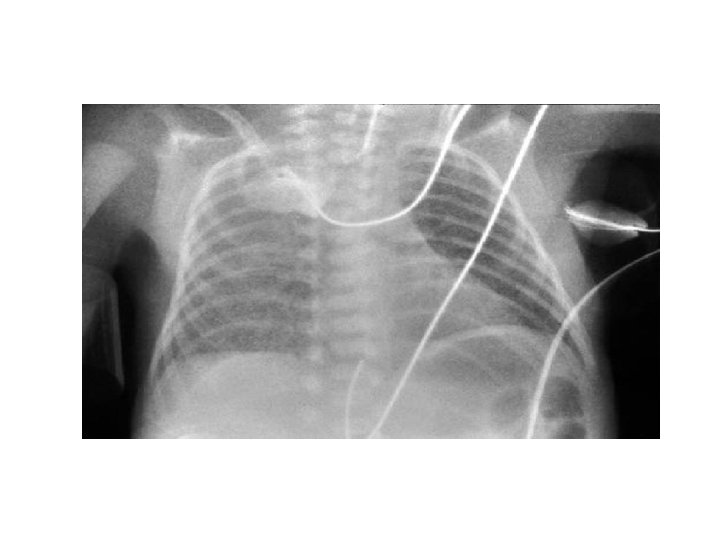

Estejam Atentos a atelectasia pela Alta Concentração de Oxigênio É muito importante que evitemos as armadilhas que MÃE NATUREZA não queria que nós caíssemos, como um fluxo livre com alta concentração de oxigênio. -Ao inspirarmos o ar, temos O 2, pouco CO 2 e o que mais tem é o nitrogênio e desse gás inerte os pulmões dependem para manter os alvéolos abertos. -Aos respiramos 21% de oxigênio o nitrogênio permanece nos alvéolos para mantê-los aberto, mas quando inspiramos O 2 em alta concentração e expiramos, isso elimina o nitrogênio. Quando o O 2 É ABSORVIDO PRINCIPALMENTE EM ÁREAS QUE ESTÃO PARCIALMENTE BLOQUEADAS essas áreas entram em colapso porque não há mais nitrogênio para manter os alvéolos abertos. -Esse é um exemplo fantástico de um bebê que desenvolveu atelectasia relacionado ao oxigênio porque recebeu uma cânula de alto fluxo com uma alta concentração de O 2. Veja esse pulmão. A doença do lado desse pulmão é totalmente diferente do outro lado. E esse bebê tinha 37 semanas de gestação. Você não esperaria uma deficiência de surfactante! (veja figura a seguir)

-Quando o liquido que sai dos pulmões e vai para os tecidos gera uma pressão intersticial que vai de 0 -6 cm. H 2 O nas primeiras 4 horas (depois fica subatmosférica: -4 cm H 2 O e permanece por toda a vida). -A parede torácica se expande para acomodar tanto a nova CFR e o líquido que sai das vias aéreas e vai para o interstício. As consequências, entretanto, com a geração de uma pressão intersticial aumentada é que o liquido vai querer voltar para as vias aéreas. Para evitar esse fato, ao oferece PEEP, gradualmente o pulmão se enche de ar e o gás permanece no final da expiração. Assim, se você não usar PEEP, o líquido está repreenchendo as vias aéreas no final de cada respiração. - A B C Em A, B: PEEP de zero; Em C: PEEP de 5 cm. H 2 O! Imaging lung aeration and lung liquid clearance at birth using phase contrast X-ray imaging. Hooper SB, Kitchen MJ, Siew ML, Lewis RA, Fouras A, te Pas AB, Siu KK, Yagi N, Uesugi K, Wallace MJ. Clin Exp Pharmacol Physiol. 2009 Jan; 36(1): 117 -25